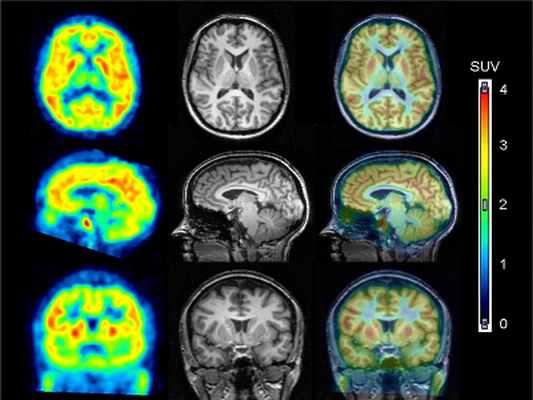

ОФЭКТ/МРТ головного мозга (гибридизация с ранее проведенным МРТ)

Применяется для дифференциальной диагностики злокачественных новообразований головного мозга с доброкачественными, инфекционными или посттерапевтическими процессами. Исследование проводится в один день через 10-15 минут после внутривенной инъекции радиофармпрепарата.

Комбинация данных, полученных при ОФЭКТ с точными анатомическими данными, полученными при РКТ, обеспечивает новый уровень диагностической информации. Применение гибридной технологии позволяет достоверно определять наличие или отсутствие патологического процесса.

Точное совмещение анатомических и функциональных изображений повышает надежность определения локализации очагов поражения. Обычно ОФЭКТ/КТ проводится сразу после планарного исследования.